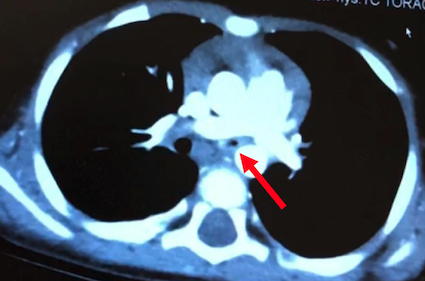

Nell’ipotesi di anello vascolare, è stata eseguita TC torace con riscontro di riduzione di calibro del tratto intermedio del bronco principale (> 90%) con rapporti di continuità con strutture vascolari e consensuale oligoemia diffusa del polmone sinistro e riduzione di calibro dei vasi arteriosi e venosi omolaterali (Figura 2).